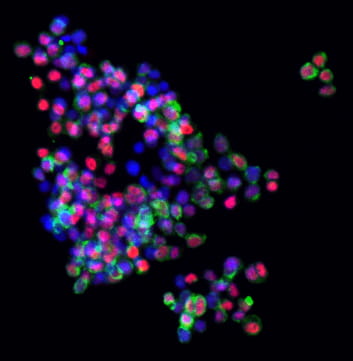

Fig. 2. Confocal immunofluorescence in a hepatoblastoma tumoroid showing heterogeneous expression of hepatobiliary lineage markers, HNF4A (red, hepatocytic) and CK19 (green, cholangiocytic).

Using these tumoroids, along with histology-guided and spatial transcriptomics of patient specimens, we determined that hepatobiliary lineage programs (Fig. 2) modify the transcriptional outcome of somatic mutations in the CTNNB1 gene, encoding the Wnt effector beta-catenin, found in up to 90% of hepatoblastomas (Wu et al., Nature Communications 2024).